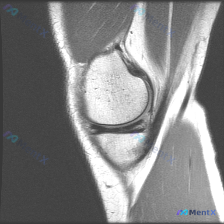

今天看到一份很有代表性的读片病例,整理出来和大家分享一下,核心问题就是:临床怀疑半月板异常,但是只给了一张膝关节矢状位T1加权MRI,阅片没发现明确异常,这个情况该怎么分析? 先整理一下这份影像资料的基本信息 这是单张膝关节正中矢状位T1加权像,图像质量清晰,没有运动伪影,能看到股骨远端、胫骨近端、...

刚看到这个有意思的读片病例,主诉提示半月板异常,但只有单张膝关节MRI T1矢状位图像,整理出来和大家分享思路。 病例核心信息 这次是影像读片场景: 1. 临床提示:怀疑存在半月板异常 2. 影像资料:仅提供单张膝关节MRI T1序列矢状位图像 影像分析所见 先给大家说下这张图的实际表现: - 骨骼...